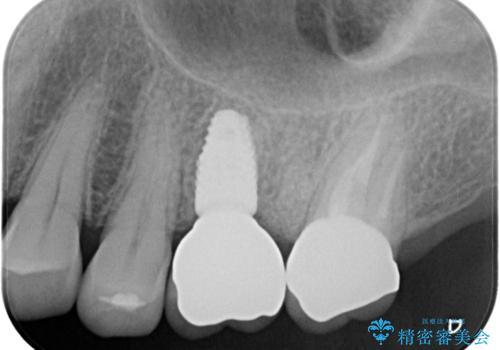

歯牙の破折を認めたため抜歯をし、インプラントにて咬合回復をしました。

抜歯後、骨増生を行ったのちインプラントを埋入しています。